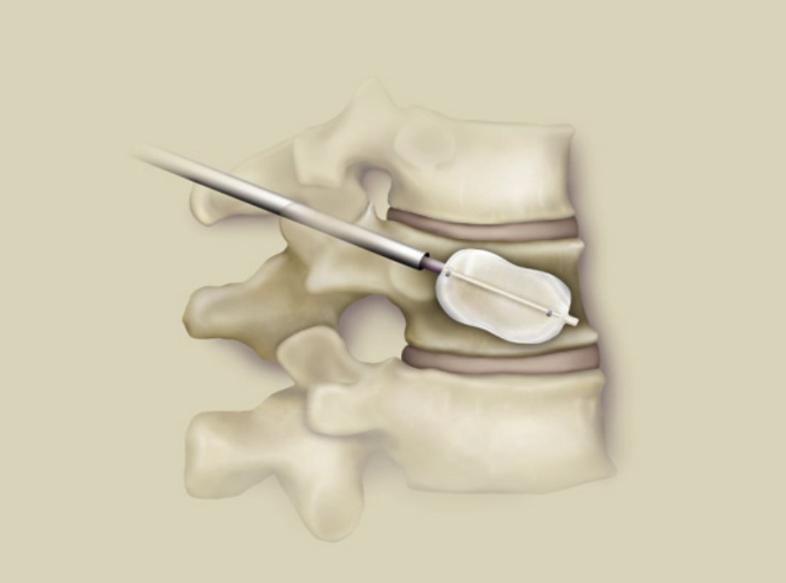

椎体成形术,没什么特殊的,常规手术微创操作。术前复查腰椎MRI时又提出异议了,三个月前查的MRI为什么还要查?无力吐槽,对我完全不信任,仔细讲解除外新发骨折,那不是查了腰椎CT了吗?再次解释除外隐匿性骨折(感觉医生并不是在看病,天天在解释)。果不其然,三个月前腰椎骨折,这次不光腰椎骨折,胸椎也有骨折(朋友并没有理解到苦心),局麻微创手术很顺利,两个小时后安返病房,患者腰痛背痛明显好转。

老太太卧床三个月,本来年纪大就骨质疏松,这三个月直接是骨质疏松程度明显加重,手术很顺利,缓解了疼痛,但是不敢让老太太下地了,她的骨头太不结实。反复告诉朋友减少下地防止再骨折。术后一个月朋友打来电话,老太太腰背部不疼了,非常满意,美中不足是不敢让下地,但是卧床护理起来简单多了,听到这个结果我很纠结,如果第一次果断告诉他手术,不要犹豫,可能现在老太太已经走出家门晒太阳了。

人生没有重来,同样治病也没有后悔药,选择了道路只能是走出什么样算什么样,谁也无法预估未来,我国太需要防治“未病"了,随着平均年龄的增多(目前是77岁),老年人还是应该选择微创手术,损伤小,恢复快,收益高。